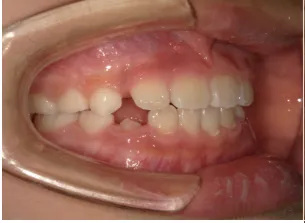

治療中③小2(7y8m):JUMP 受け口が改善

| 行ったご提案・診断内容 | 成長期に行う治療と咬合治療をご提案 受け口用ファンクショナルアプライアンス(写真②③)からスタートし、小2以降で上下顎の拡大・歯列弓の形態修正・前歯の並べ直し(写真④)を行いその後、モノブロック(筋機能的咬合誘導)装置(写真⑤)へ移行し、受け口の再発予防と永久歯を適切な咬み合わせに誘導し、必要によりマルチブラケット法へ移行する治療方法を提案しました。 成長期治療(成長時期にお口の環境を整える治療) 2年生以降から 咬合治療 |